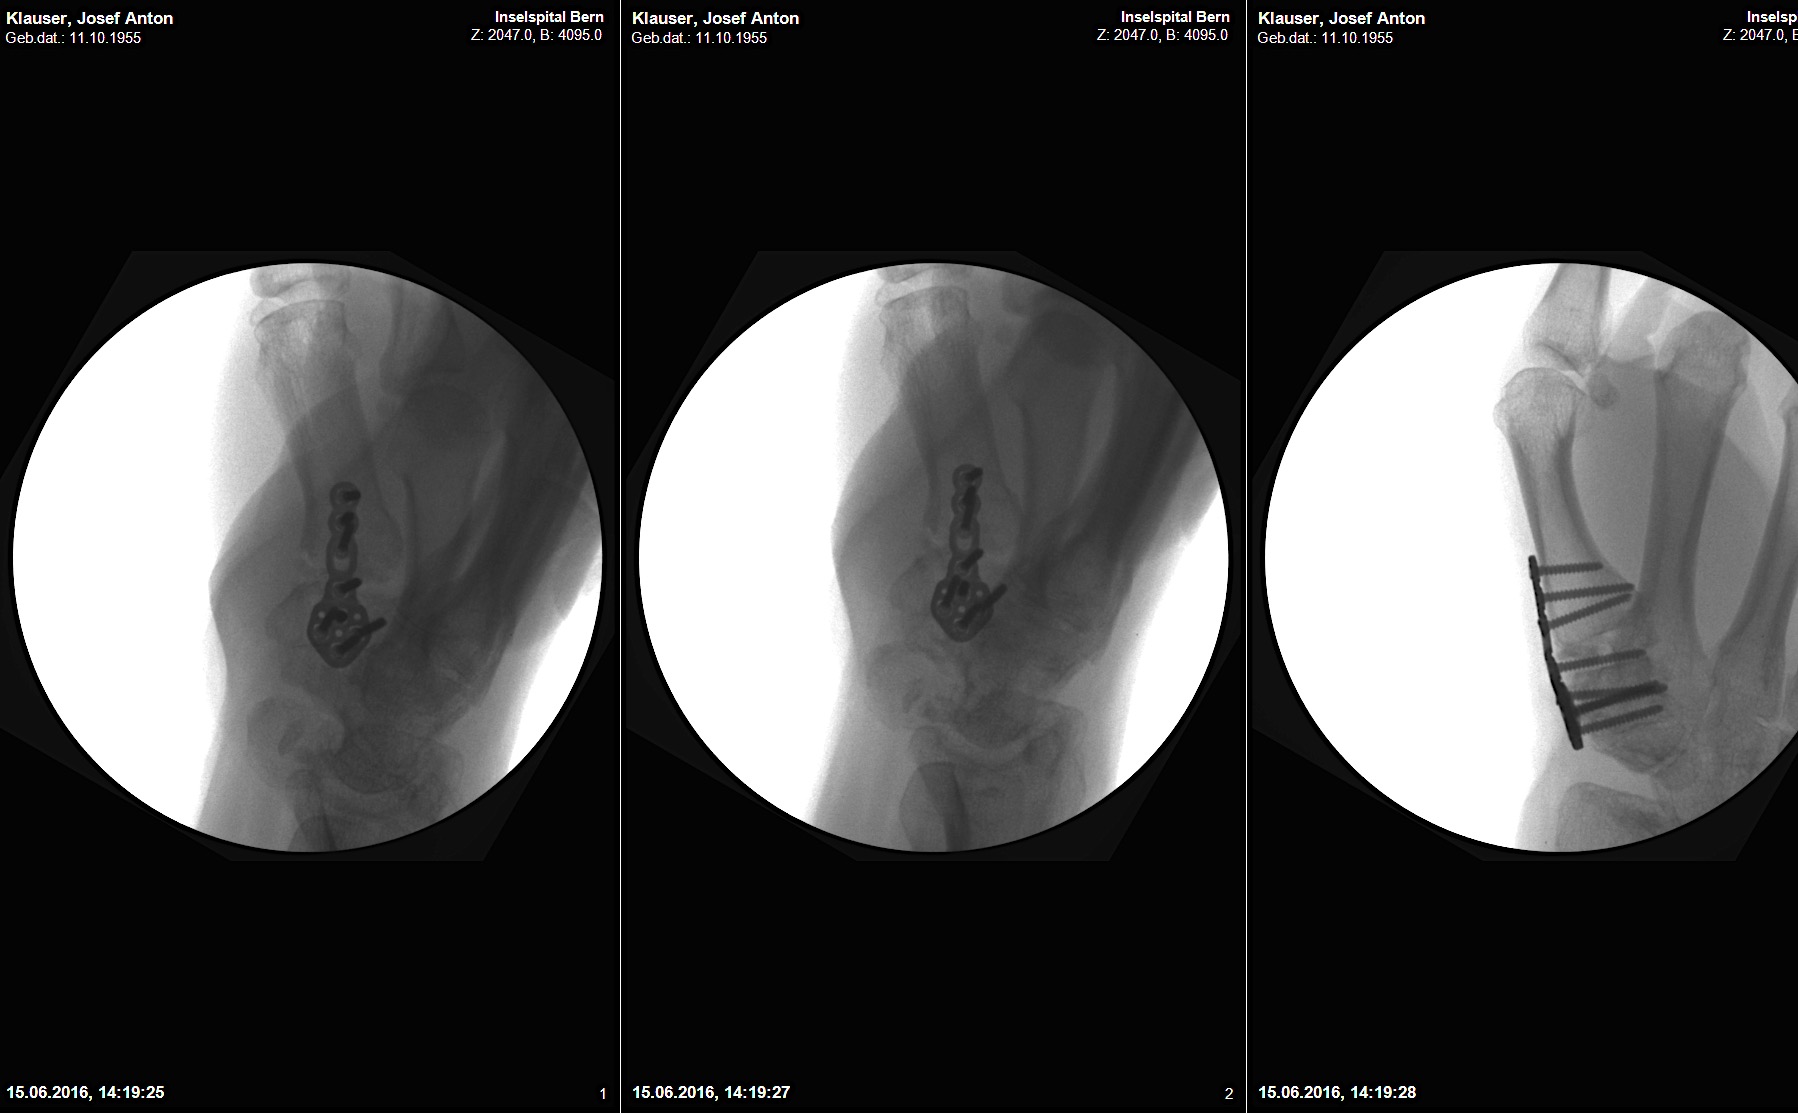

A 60-year-old male patient required an arthrodesis of the thumb carpometacarpal (CMC) joint after an implant arthroplasty in conjunction with the implantation of cortico-cancellous bone graft following a proximal row carpectomy and a previous arthrodesis between trapezium-trapezoid and the 2nd CMC joint (Fig 9). The first metacarpal dorsal plate from the VA Locking Hand System was selected for the procedure (Figs 10 - 11).